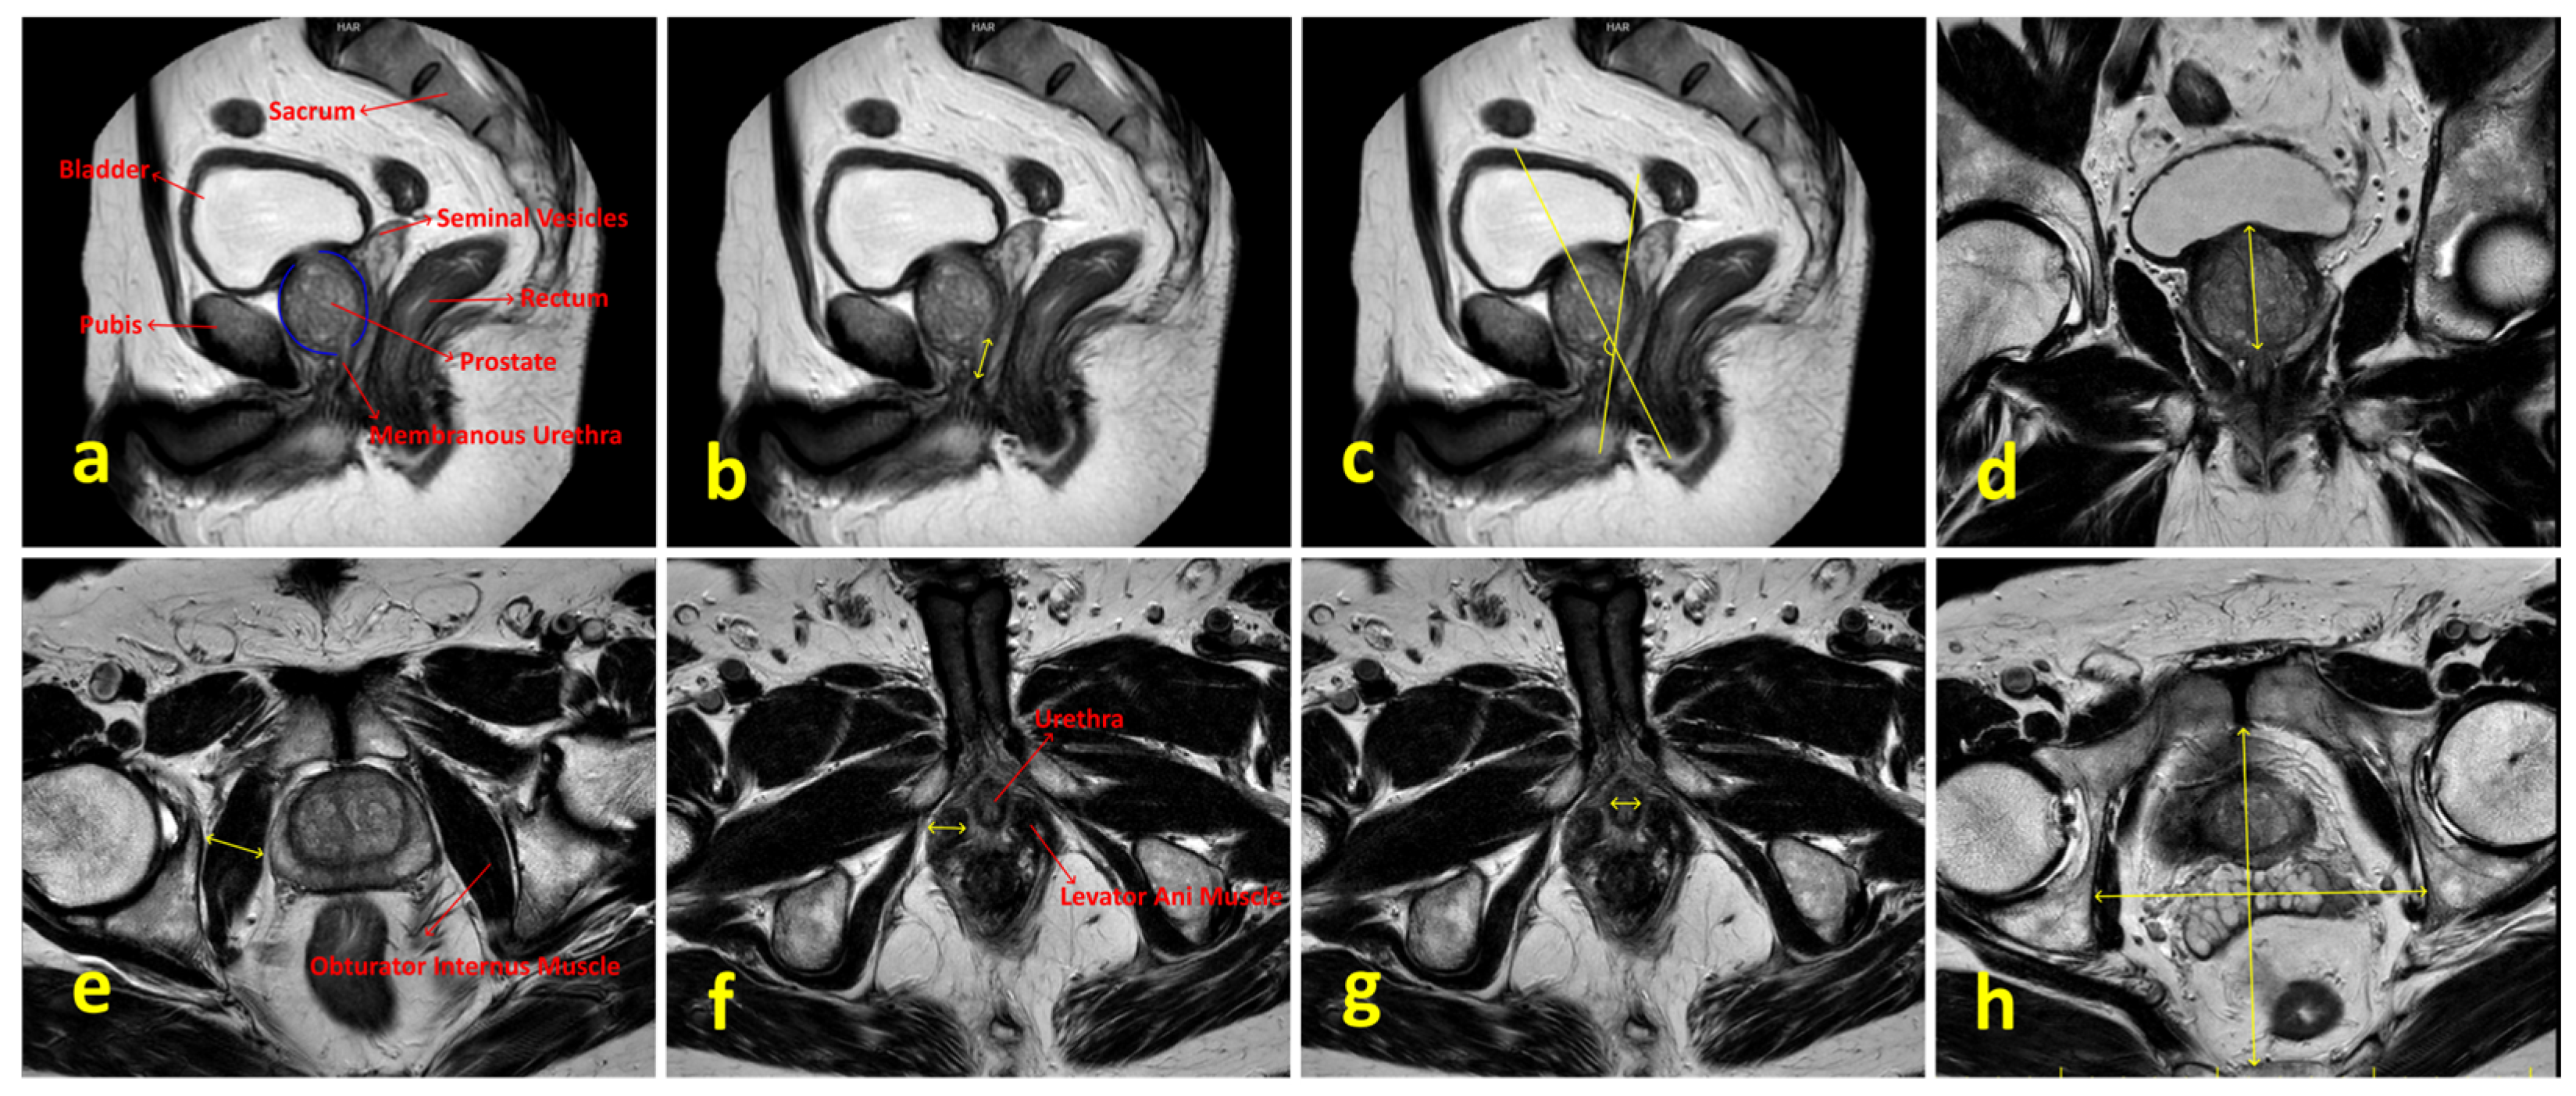

| Membranous urethral length (mm) | 14.5 (10.6–24.8) | 15.6 (10.6–21.4) | 15.8 (11.8–21.4) | 0.101 c |

| Membranous urethra–prostate axis angle | 56.6 (33.6–77.5) | 55.2 (32.7–86.6) | 59.4 (44.3–76.4) | 0.531 c |

| Obturator internus muscle thickness (mm) | 19.9 (13.4–25.9) | 20.3 (15.4–27.4) | 20.3 (13–27.7) | 0.900 c |

| Levator ani muscle thickness (mm) | 9.9 (6.3–14.9) | 10.5 (6.8–12.2) | 10.4 (8.5–12.4) | 0.825 c |

| Urethral width (mm) | 10.8 (6.7–13.9) | 9.6 (7–12.4) | 10.1 (8.3–14.1) | 0.012 c |

| Intraprostatic urethral Length (mm) | 32.4 (20.7–56.6) | 36.1 (19–57.6) | 35.2 (29–52.5) | 0.079 a |

| Pelvis AP diameter (mm) | 124.9 (101.5–141.6) | 128.4 (119–139.8) | 121.2 (80.5–134.7) | 0.033 a |

| Pelvis transverse diameter (mm) | 117.4 (96.5–146.1) | 121.2 (103.1–151.3) | 114 (96.8–132.8) | 0.002 a |